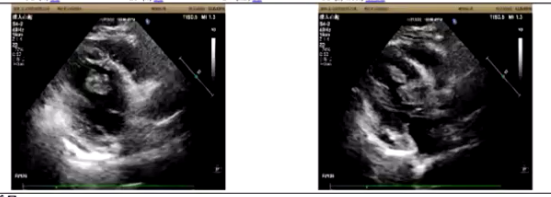

超声:甲状腺超声发现右侧甲状腺上及中部4A类实性结节,甲状旁腺区正常;腹部超声提示轻度脂肪肝;外阴超声显示双侧睾丸实质内多发钙化灶及左侧睾丸实质内低回声结节(考虑良性);心脏超声发现左室腔内两个实性占位,考虑心脏肿瘤,伴少量心包积液;甲状腺超声造影提示甲状腺结节级别上升为TI-RADS 4B类。

根据Carney复合征的治疗原则,结合患者情况,因心脏肿瘤有明确基底且超声心动图显示摆动,建议先行心脏手术,二期择期行肾上腺手术,术前口服米非司酮准备。患者在北京协和医院心脏外科行全麻低温体外循环下左心室肿瘤切除术,术后病理提示符合黏液瘤局部伴钙化和骨化。四个月后行右侧肾上腺肿瘤切除术,病理提示右肾上腺嗜酸性肾上腺皮质腺瘤生长活跃,周边可见多发富色素小皮质结节形成。目前甲状腺手术尚未进行,睾丸占位及钙化灶在随访中,骨密度未进一步复查。